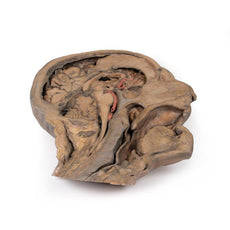

Posterior view of the pharynx: The superior, middle and inferior pharyngeal constrictors are indicated on the pharynx wall. The oesophagus can be identified emerging from the lower end of the pharynx. The posterior horn of the hyoid bone acts as a useful landmark. The carotid sheath seen from behind clearly shows the vagus nerve and its pharyngeal branches on the left. The recurrent laryngeal nerve is briefly visible on the left lying medial to the inferior thyroid artery. The occipital arteries are visible as they curve around the mastoid process. The vertebral arteries are seen either side of the brainstem as they enter the foramen magnum. The cerebellum has been removed to allow the fourth ventricle to be exposed. The cut surfaces of the cerebellar peduncles are clearly visible. A large portion of the posterior inferior cerebellar artery on the right is still visible as it winds around around the brainstem.

Posterior view of the pharynx: The superior, middle and inferior pharyngeal constrictors are indicated on the pharynx wall. The oesophagus can be identified emerging from the lower end of the pharynx. The posterior horn of the hyoid bone acts as a useful landmark. The carotid sheath seen from behind clearly shows the vagus nerve and its pharyngeal branches on the left. The recurrent laryngeal nerve is briefly visible on the left lying medial to the inferior thyroid artery. The occipital arteries are visible as they curve around the mastoid process. The vertebral arteries are seen either side of the brainstem as they enter the foramen magnum. The cerebellum has been removed to allow the fourth ventricle to be exposed. The cut surfaces of the cerebellar peduncles are clearly visible. A large portion of the posterior inferior cerebellar artery on the right is still visible as it winds around around the brainstem.